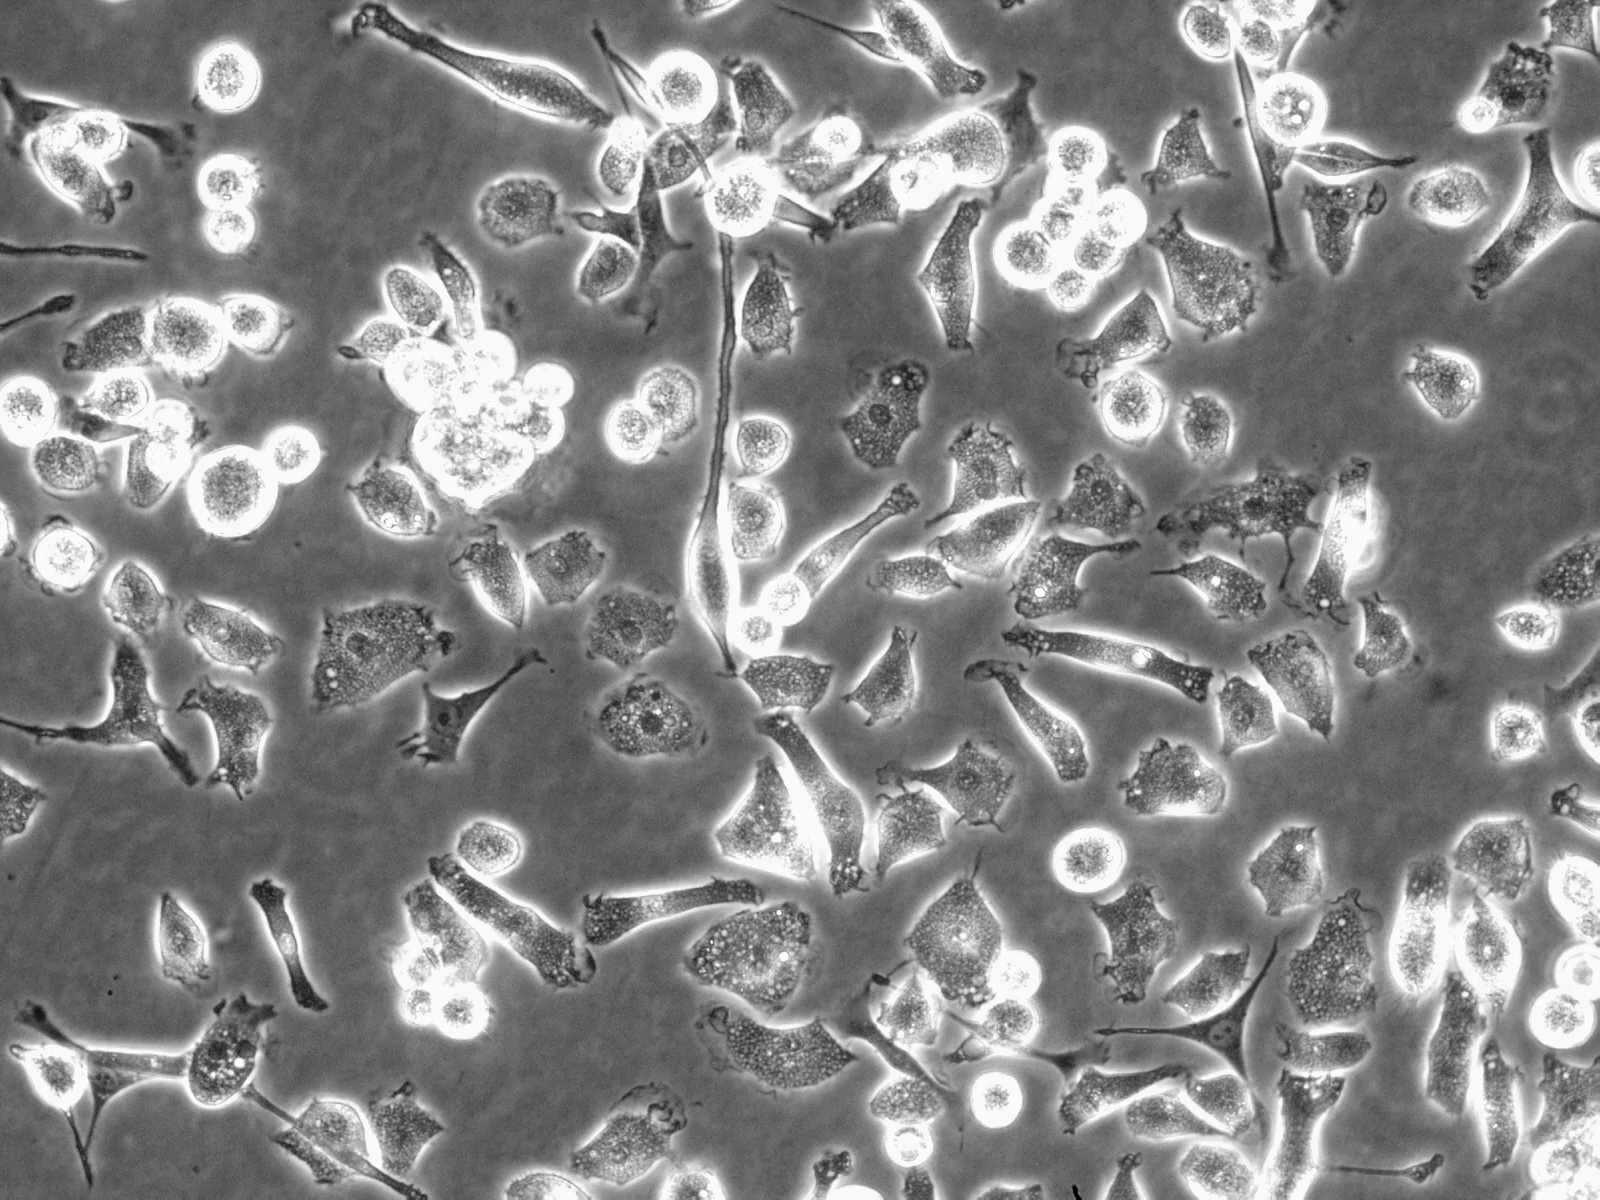

Rat Hepatic Macrophage

Sample Type:

Isolated Cells